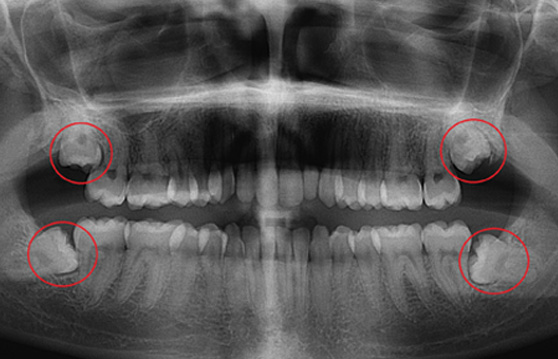

´õÁÁÀº¼­¿ïÄ¡°ú¿¡¼­´Â ¿¢½º·¹ÀÌ Àåºñ, ÷´Ü CT µî »ç¶û´Ï ¹ßÄ¡ Áø´Ü¿¡ ÇÊ¿äÇÑ Ã·´Ü Àåºñ¸¦ º¸À¯Çϰí ÀÖ¾î ¾ÈÀüÇÑ »ç¶û´Ï ¹ßÄ¡°¡ °¡´ÉÇÕ´Ï´Ù.